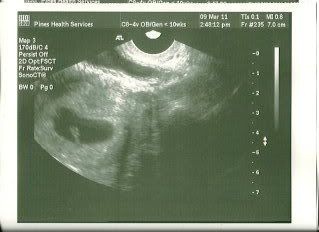

So we had our first ultrasound today... and we're having: A GRAIN OF RICE!

Baby measures at 7weeks0days, and there's a HEARTBEAT! I can't tell you how happy that makes me! Considering the last U/s I had there was a sac but no baby & no heartbeat this makes us ecstatic!

Our EDD will stay at Oct 25

Crossing fingers that everything stays good. The midwife says that now that we've seen a heartbeat the chance for miscarriage goes from 30-35% down to 2-4% so yay!